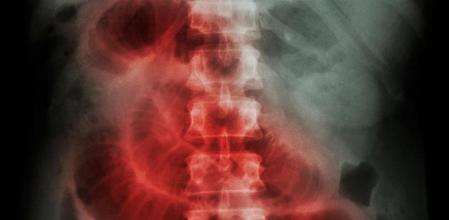

Obstrucción intestinal.

Obstrucción intestinal. (Foto: Fuente Externa)

La obstrucción intestinal causa dolor intenso y malestar estomacal